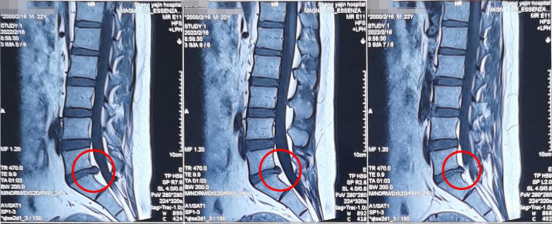

术前影像学资料

陕西冶金医院神经脊柱科的张少华主任、熊东主任接诊后,为小孙进行了详细的查体,并结合各项检查结果和影像学片子,发现他在腰5/骶1节段出现了比较严重的腰椎间盘突出,并造成较为严重的神经受压。

考虑到患者比较年轻,我们为他选择了微创的椎间孔镜手术。术后5天查房时,小孙的腰疼以及右腿的疼麻已经消失,走路已经可以健步如飞、大步行走,和正常人一般无二。